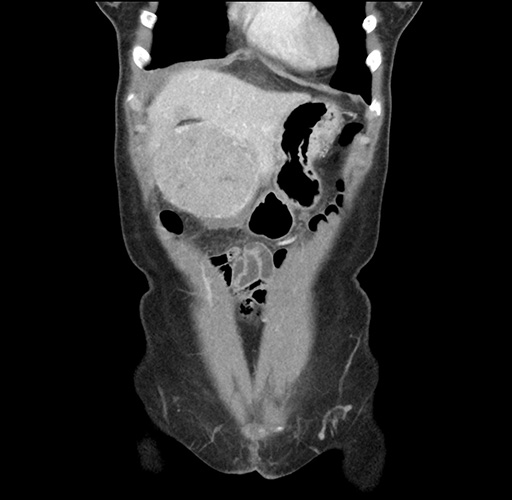

Imaging Analysis

Look through the patient's CT scan to identify any areas of concern for the necessary procedure.

Based on your CT findings, which issue(s) would give reason for "planned slowing down moment(s)" in this case?

Considering a standard left lateral sectionectomy procedure, what step(s) of the operation would you do differently in this case ?